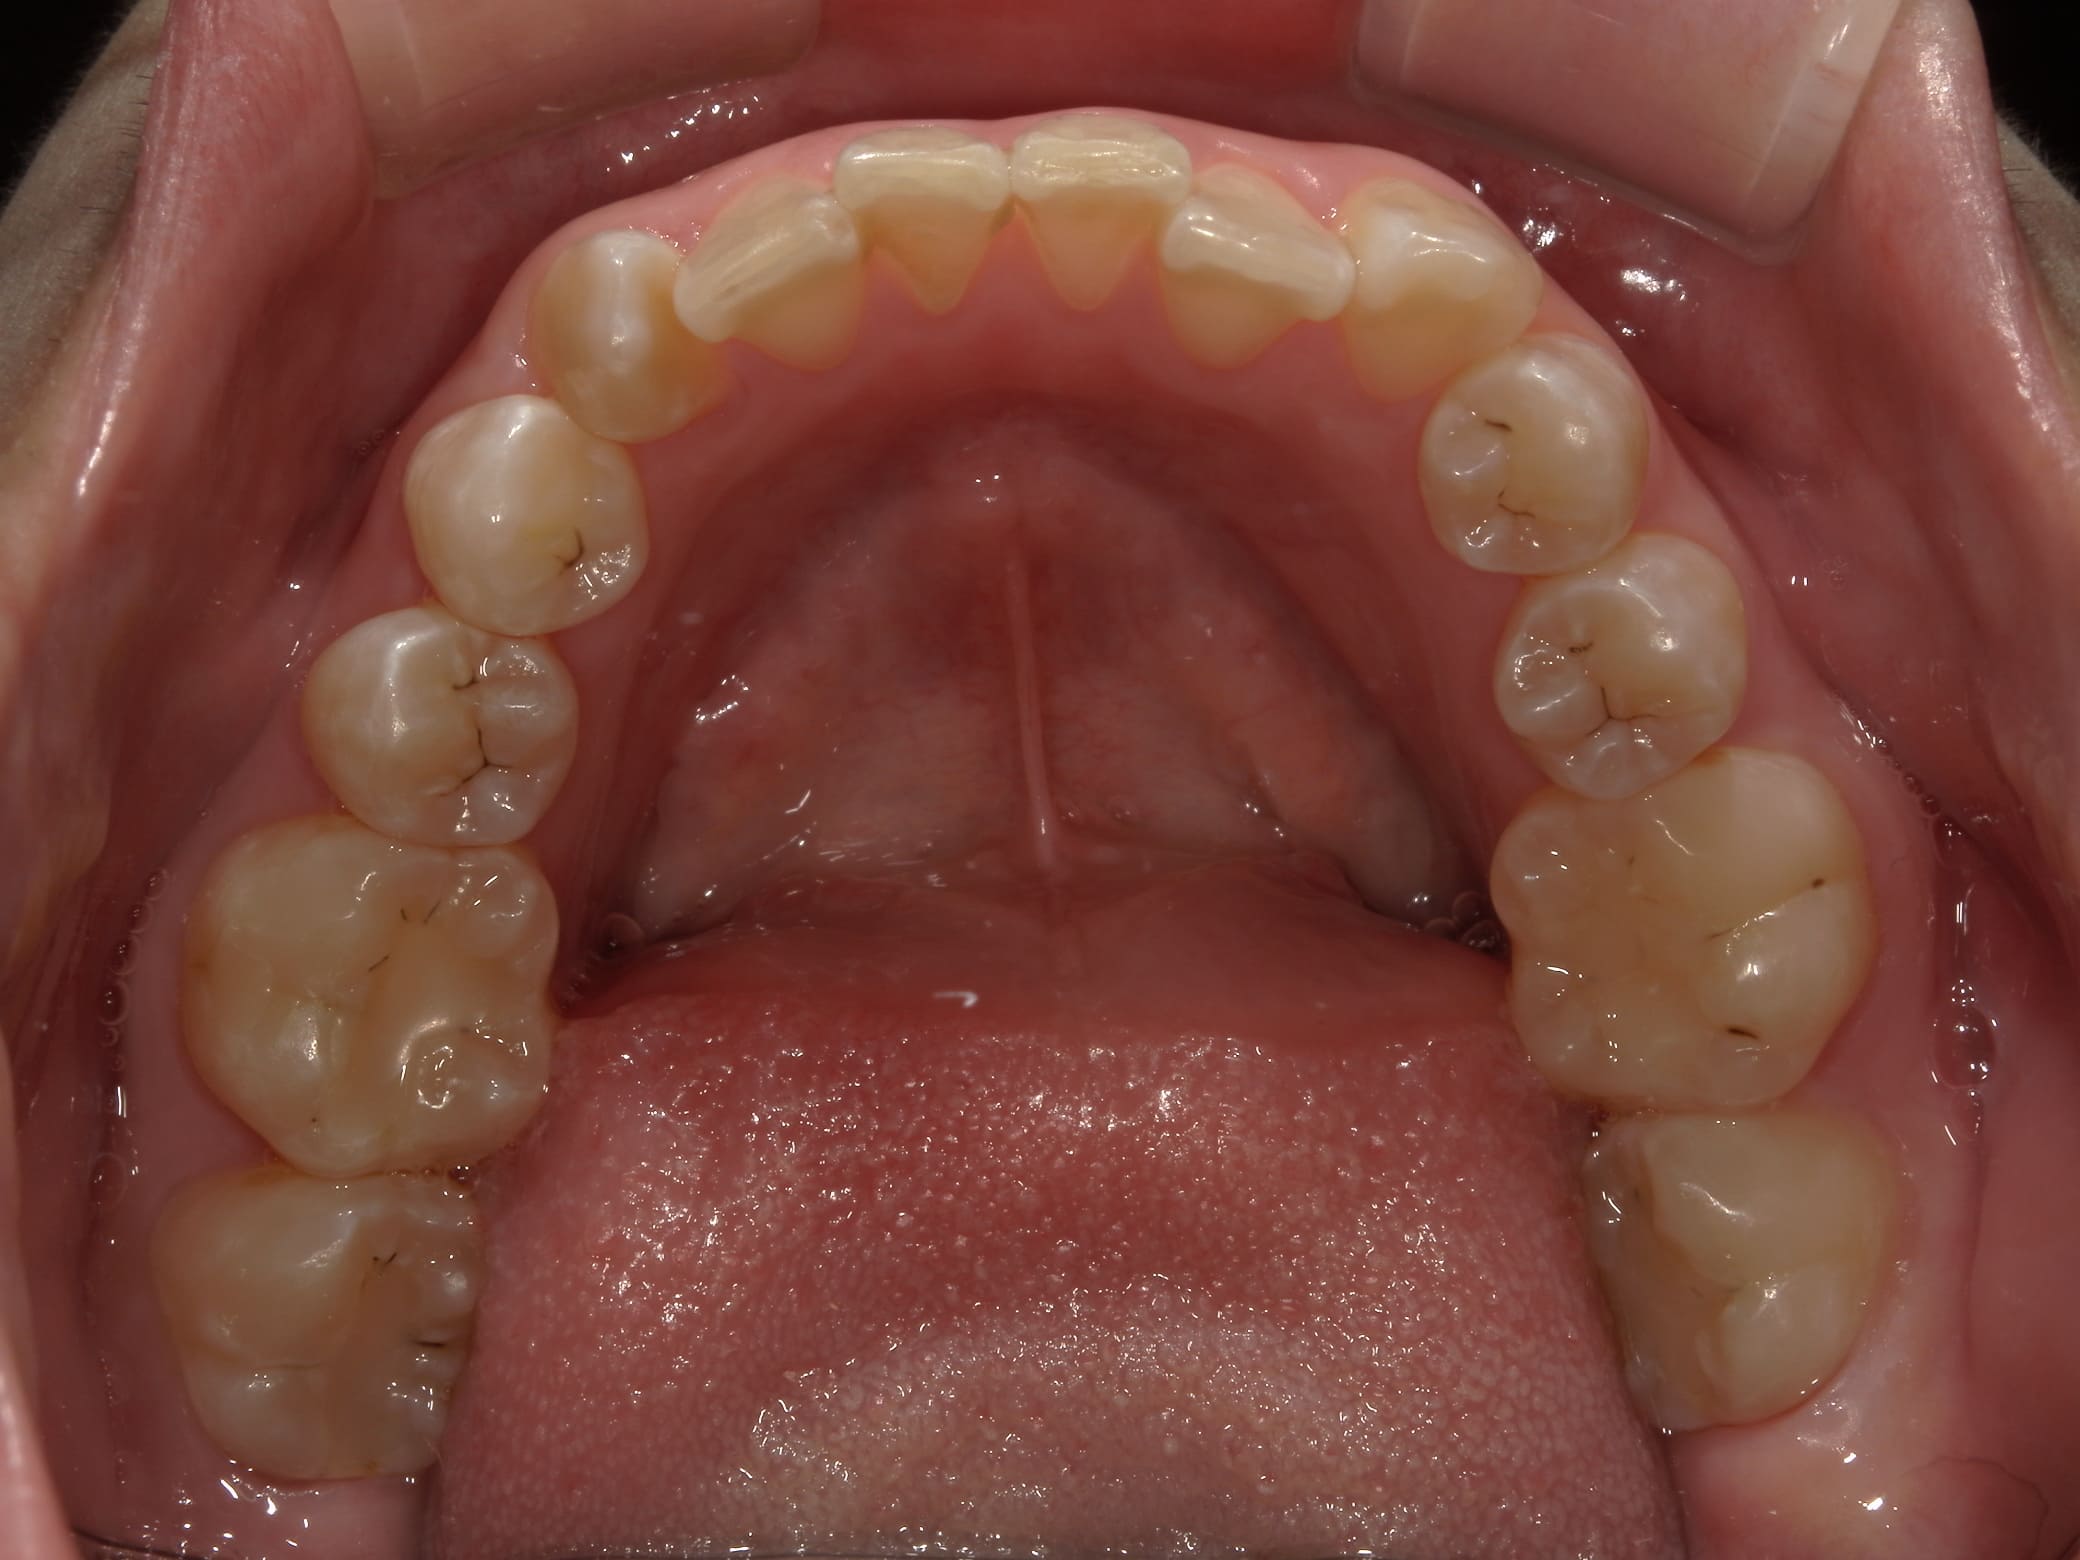

| 主訴 | 叢生が気になる |

| 治療期間・回数 | 1年9ヶ月 |

| 費用 | 1,011,000円 |